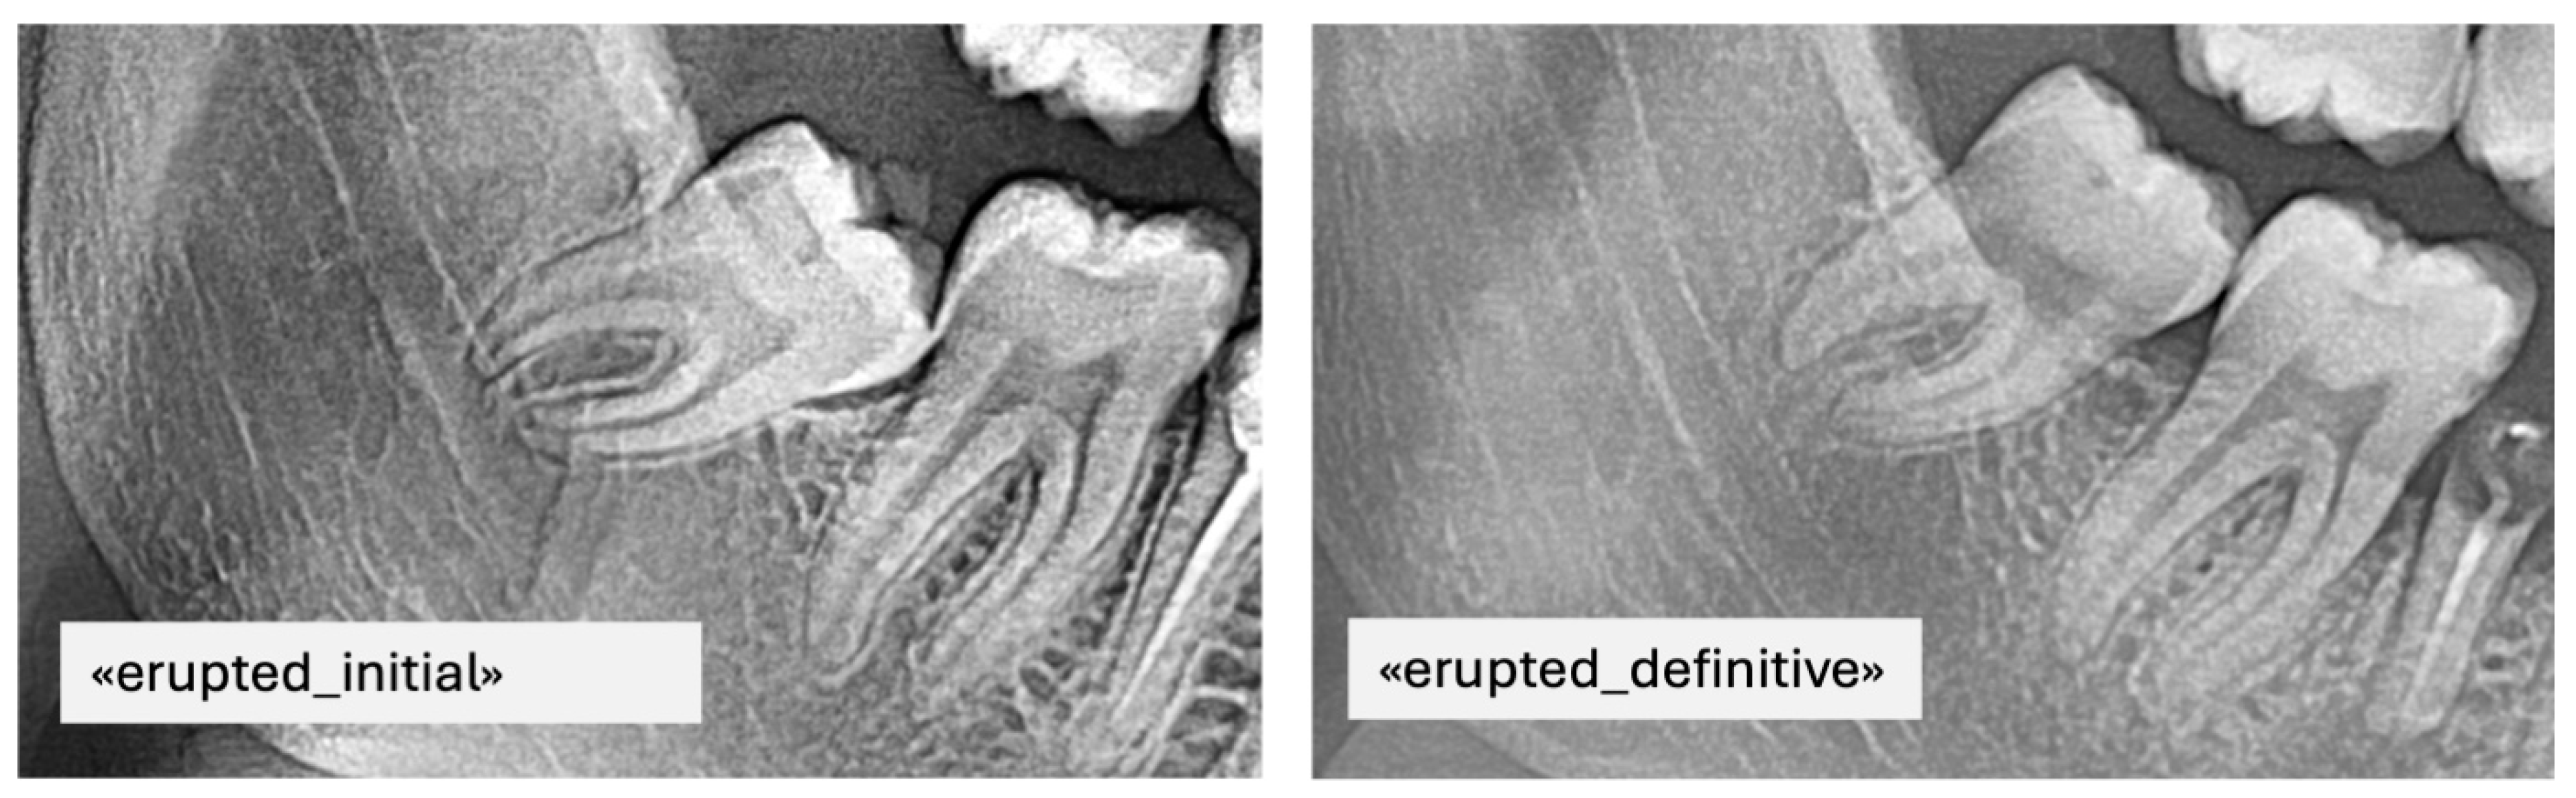

- Erupted: the occlusal surface of the third molar was at or above the occlusal plane of the adjacent second molar, with no overlying bone visible radiographically.

- Impacted: the third molar was entirely below the occlusal plane, with full bone coverage and/or evident spatial limitation or unfavorable angulation (e.g., mesioangular or horizontal position) in relation to the second molar.